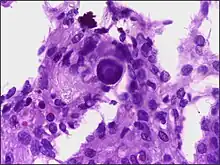

Although the majority of meningiomas are benign, they may have malignant presentations. Classification of meningiomas are based upon the WHO classification system.[24]

- Benign (Grade I) – (90%) – meningothelial, fibrous, transitional, psammomatous, angioblastic

- Atypical (Grade II) – (7%) – chordoid, clear cell, atypical (includes brain invasion)

- Anaplastic/malignant (Grade III) – (2%) – papillary, rhabdoid, anaplastic (most aggressive)

In a 2008 review of the latter two categories, atypical and anaplastic-meningioma cases, the mean overall survival for atypical meningiomas was found to be 11.9 years vs. 3.3 years for anaplastic meningiomas. Mean relapse-free survival for atypical meningiomas was 11.5 years vs. 2.7 years for anaplastic meningiomas.[25]

Malignant anaplastic meningioma is aggressive. Although anaplastic meningioma has higher chances of distant metastasis than the other two types, the overall incidence of meningioma metastasis is only 0.18%; which is considered rare.[26] Even if, by general rule, neoplasms of the nervous system (brain tumors) cannot metastasize into the body because of the blood–brain barrier, anaplastic meningioma can. Although they are inside the cerebral cavity, they are located on the bloodside of the BBB, because meningiomas tend to be connected to blood vessels. Thus, cancerized cells can escape into the bloodstream, which is why meningiomas, when they metastasize, often turn up around the lungs.

Anaplastic meningioma and hemangiopericytoma are difficult to distinguish, even by pathological means, as they look similar, especially, if the first occurrence is a meningeal tumor, and both tumors occur in the same types of tissue.